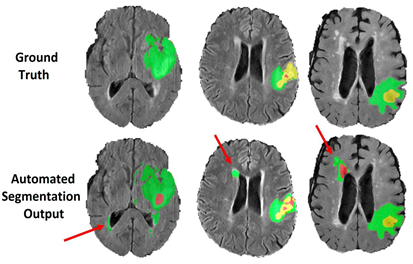

To facilitate the annotation process for BraTS 2021, initial automated segmentations were generated by fusing previously top-performing BraTS methods. The specific methods fused were the DeepMedic [28], DeepScan [27], and nnU-Net [26], all trained on the BraTS 2020 dataset [11, 12, 13]. The STAPLE label fusion [25] was used to aggregate the segmentation produced by each of the individual methods, and account for systematic errors generated by each of them separately. All these segmentation methods and the exact pipeline used to generate the fused automated segmentation has been made publicly available through the Federated Tumor Segmentation (FeTS) platform444https://www.med.upenn.edu/cbica/fets/ [39].

The volunteer neuroradiology expert annotators were provided with four mpMRI scans along with the fused automated segmentation volume to initiate the manual refinements. The ITK-SNAP [40] software was used for making these refinements. Once the automated segmentations were refined by the annotators, two senior attending board-certified neuroradiologists with more than 15 years of experience each, reviewed the segmentations. Depending upon correctness, these segmentations were either approved or returned to the individual annotator for further refinements. This process was followed iteratively until the approvers found the refined tumor sub-region segmentations acceptable for public release and the challenge conduction.

2.1.5 Common errors of automated segmentations

Building upon observations during all previous BraTS instances, we note some common errors in the automated segmentations. The most typical such errors observed are:

The choroid plexus and areas of T1 bright blood products (when they can be discriminated by comparing with the pre contrast T1 images), have erroneously been labelled as ED (Fig. 2(a)).

Vessels within the peritumoral T2 FLAIR edematous area, have been marked as ET (Fig. 2(b)).

Vessels within the peritumoral T2 FLAIR edematous area, have been marked as ED (Fig. 2(c)).

Periventricular white matter hyperintensities being confused and segmented as tumor/peritumoral regions (Fig. 2(d)).

Figure 2: Common errors expected from the automatic segmentations.